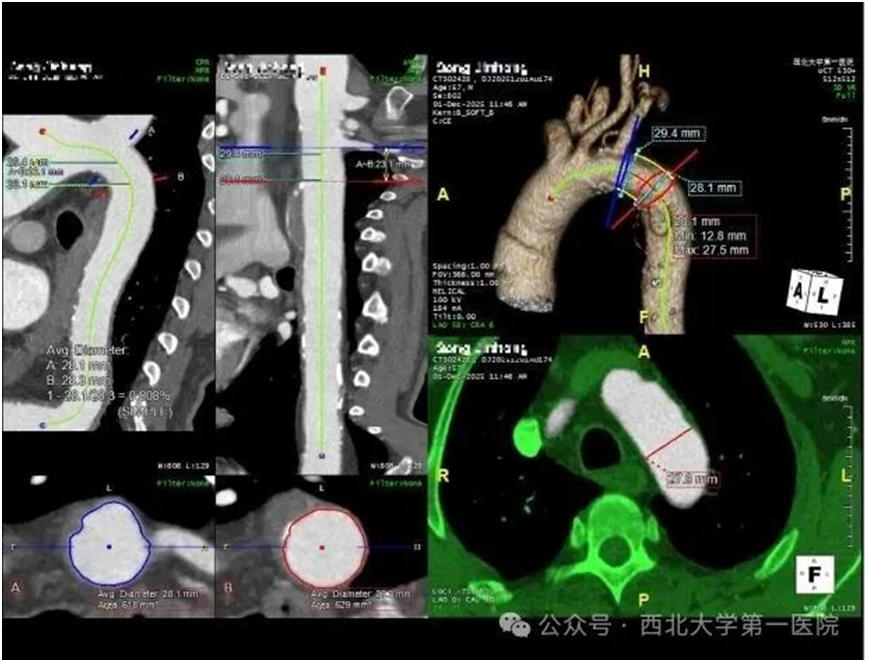

第一步:主动脉腔内隔绝术,给血管“补漏洞”

手术无需开胸开腹,仅在大腿根部做几毫米小切口,通过导管将定制覆膜支架送到主动脉溃疡处,精准覆盖破损面,把血肿和血流隔离开。这就像给血管破洞贴了“防水创可贴”,既阻止血肿破裂,又不影响正常血流,创伤小、出血少,术后患者血压稳定,出血风险解除。